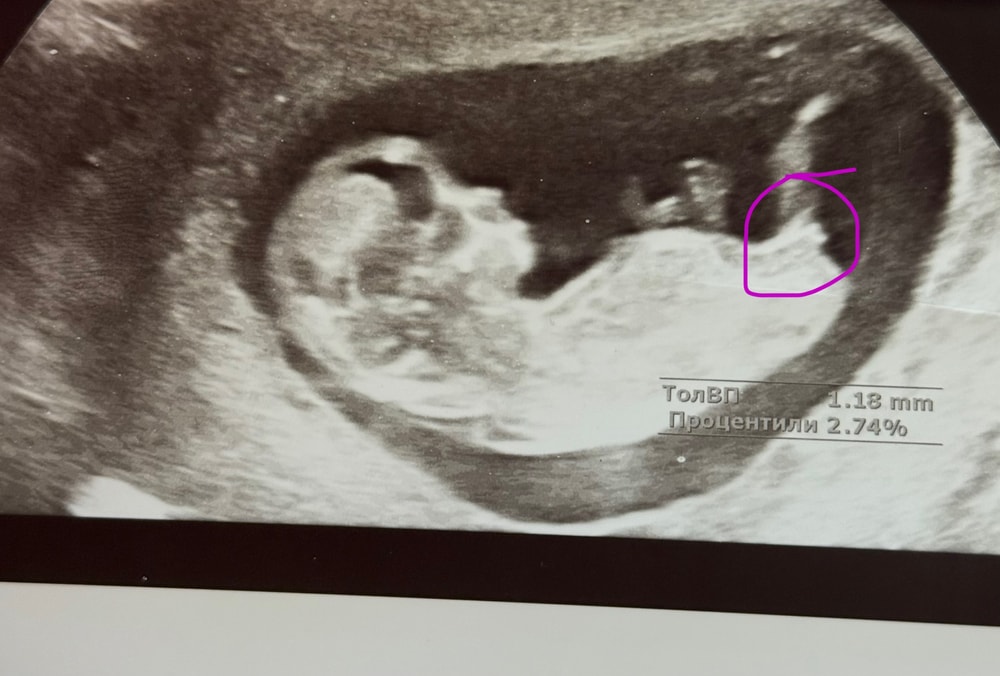

по бугорку на кого похож?

Пол малышаДевочки на кого пол похож?у кого был бугорок такой ?? и какой был пол)

Катя, чуть приподнят , сомнительно , ровно в 12 недель скрининг делала

Meli Browskudrovo, он вверх немного, у моего сына так было. Я тоже хотела дочку и надеялась, что этот угол небольшой это не мальчик